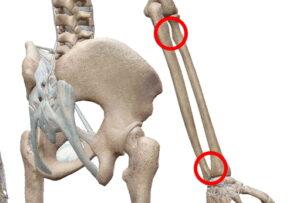

例えば、骨幹と骨端の間にある骨幹板や第一肋骨と胸骨柄を繋ぐ硝子軟骨がそれに当たります。

どちらも骨の成長が止まる10代後半~20代前半には骨化します。